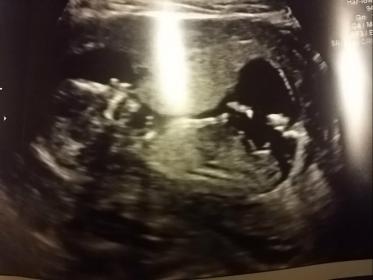

I had my first ultrasound today at 15 weeks.

I'm trying to look for a nub to tell the gender, but i'm having no luck :(

I would guess boy.

where are you guys seeing the nub? If i'm looking at what youre looking at, it looks to be pointing down....doesnt that mean girl? : o

The white spot over the flat line is what makes me guess boy.